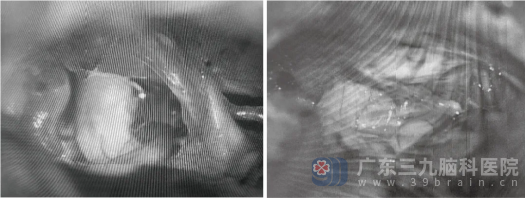

征得患者及家属同意后,患者在全麻下接受右侧桥小脑角区占位切除术联合三叉神经微血管减压术。手术采用右侧乙状窦后入路,显微镜下精准磨开内听道后壁,见黄白色肿瘤位于右侧桥小脑角区,质地中等。手术过程中精细分离血管,采用包膜内雕刻式切除方式,完整保护了面神经和耳蜗神经,全切肿瘤。术中还发现右侧小脑前下动脉分支压迫三叉神经,这正是为何患者会出现右上方牙痛症状的原因。医生垫入Teflon棉将血管与神经隔离,解决牙痛问题。

术中